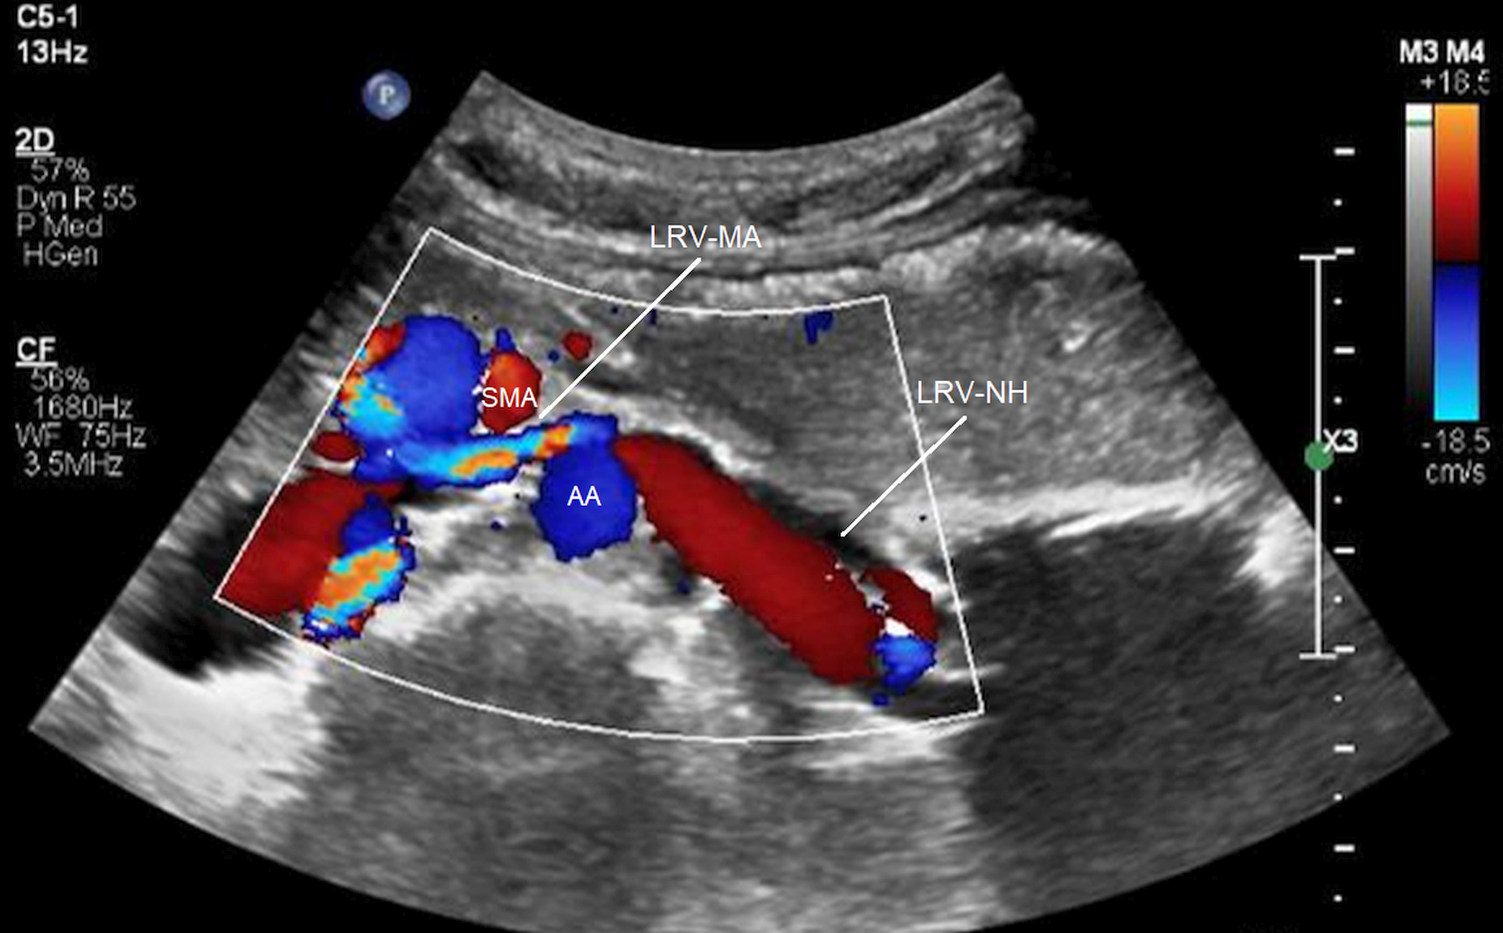

Kim and coworkers (31, 32) analyzed duplex ultrasound results of the left renal vein in 16 patients with RVCS and 18 healthy control subjects. They measured the diameters and PSVs in two regions of the left renal vein: firstly, between the SMA and the aorta (MA) and secondly, near the hilar (NH) (Figure 4). They recommended ultrasound criteria for RVCS of diameter ratio (NH/MA) > 5 (sensitivity: 69% and specificity: 89%) and PSV ratio (MA/NH) > 5 (sensitivity: 80% and specificity: 94%). Yang and colleagues (33) reported eight cases of PNCS and described their ultrasound diagnostic criteria for PNCS as follows: firstly, the finding of a retroaortic left renal vein; secondly, the diameter of the dilated part of the left renal vein (D-VD): diameter of stenotic part of the vein (S-VD) >3:1 in the supine position, or >4:1 in the spinal extension position; and thirdly, the PSV in the stenotic part of the left renal vein: PSV in the dilated part of the vein >3:1, or >4:1 in the spinal extension position.

Figure 4

Compression of the left renal vein on color Doppler imaging. SMA, superior mesenteric artery; AA, abdominal aorta; LRV-MA, left renal vein between the SMA and AA; LRV-NH, left renal vein near the hilar [from: Kim (32). Reprinted with permission from Dr Kim].